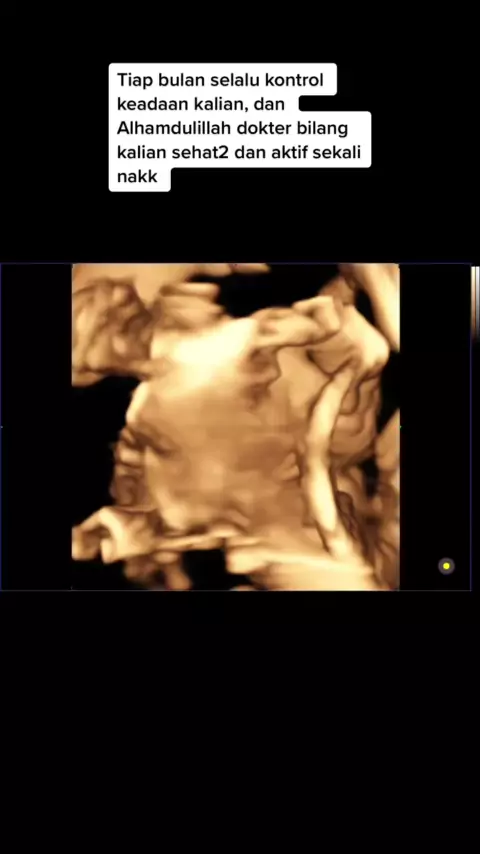

Ngeditnya sambil netesin air mata 🥹##pejuangnicu#bayihebat#babytwin#dongggggggg